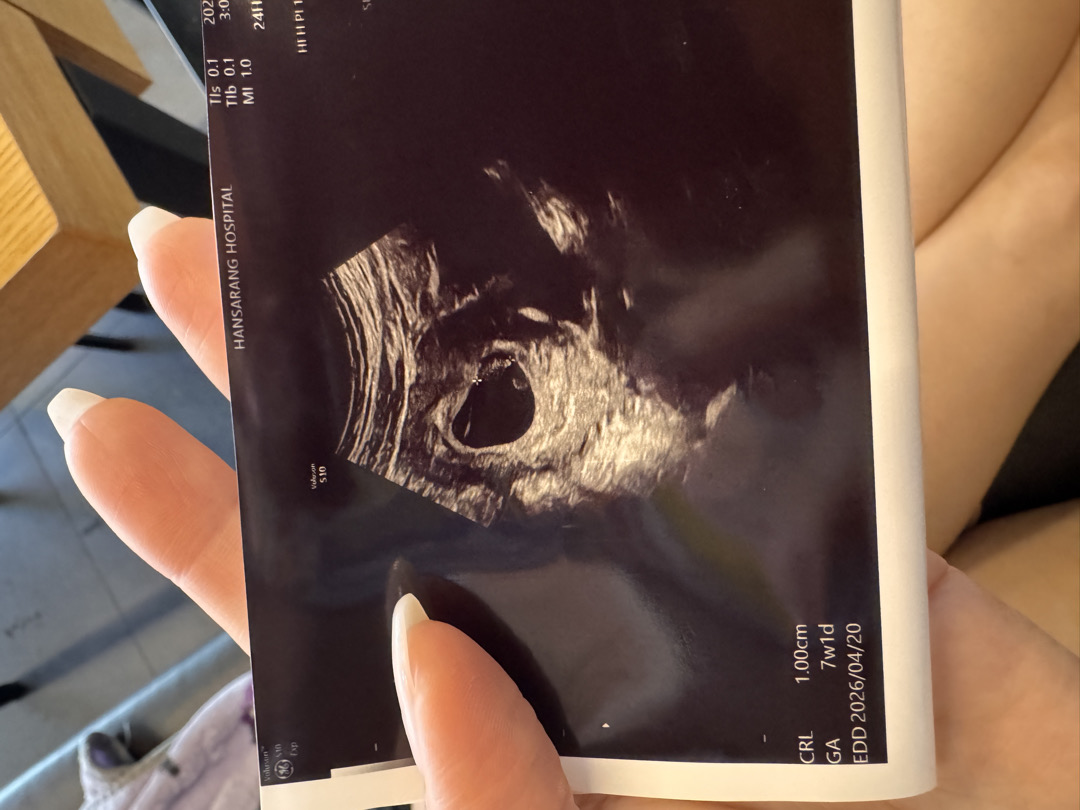

7주2일 ㅇㅅㅇ 딸일까아들일까..

난황위치로도 추측하고 심장소리로도 추측하던데 말발굽 소리이긴 했눈데.. 딸일지 아들일지 너무 설레구 궁금하구 !!!!! ㅠㅁ ㅠ 오른쪽에 강낭콩 찰싹 있어서 넘귀엽구 그래오..